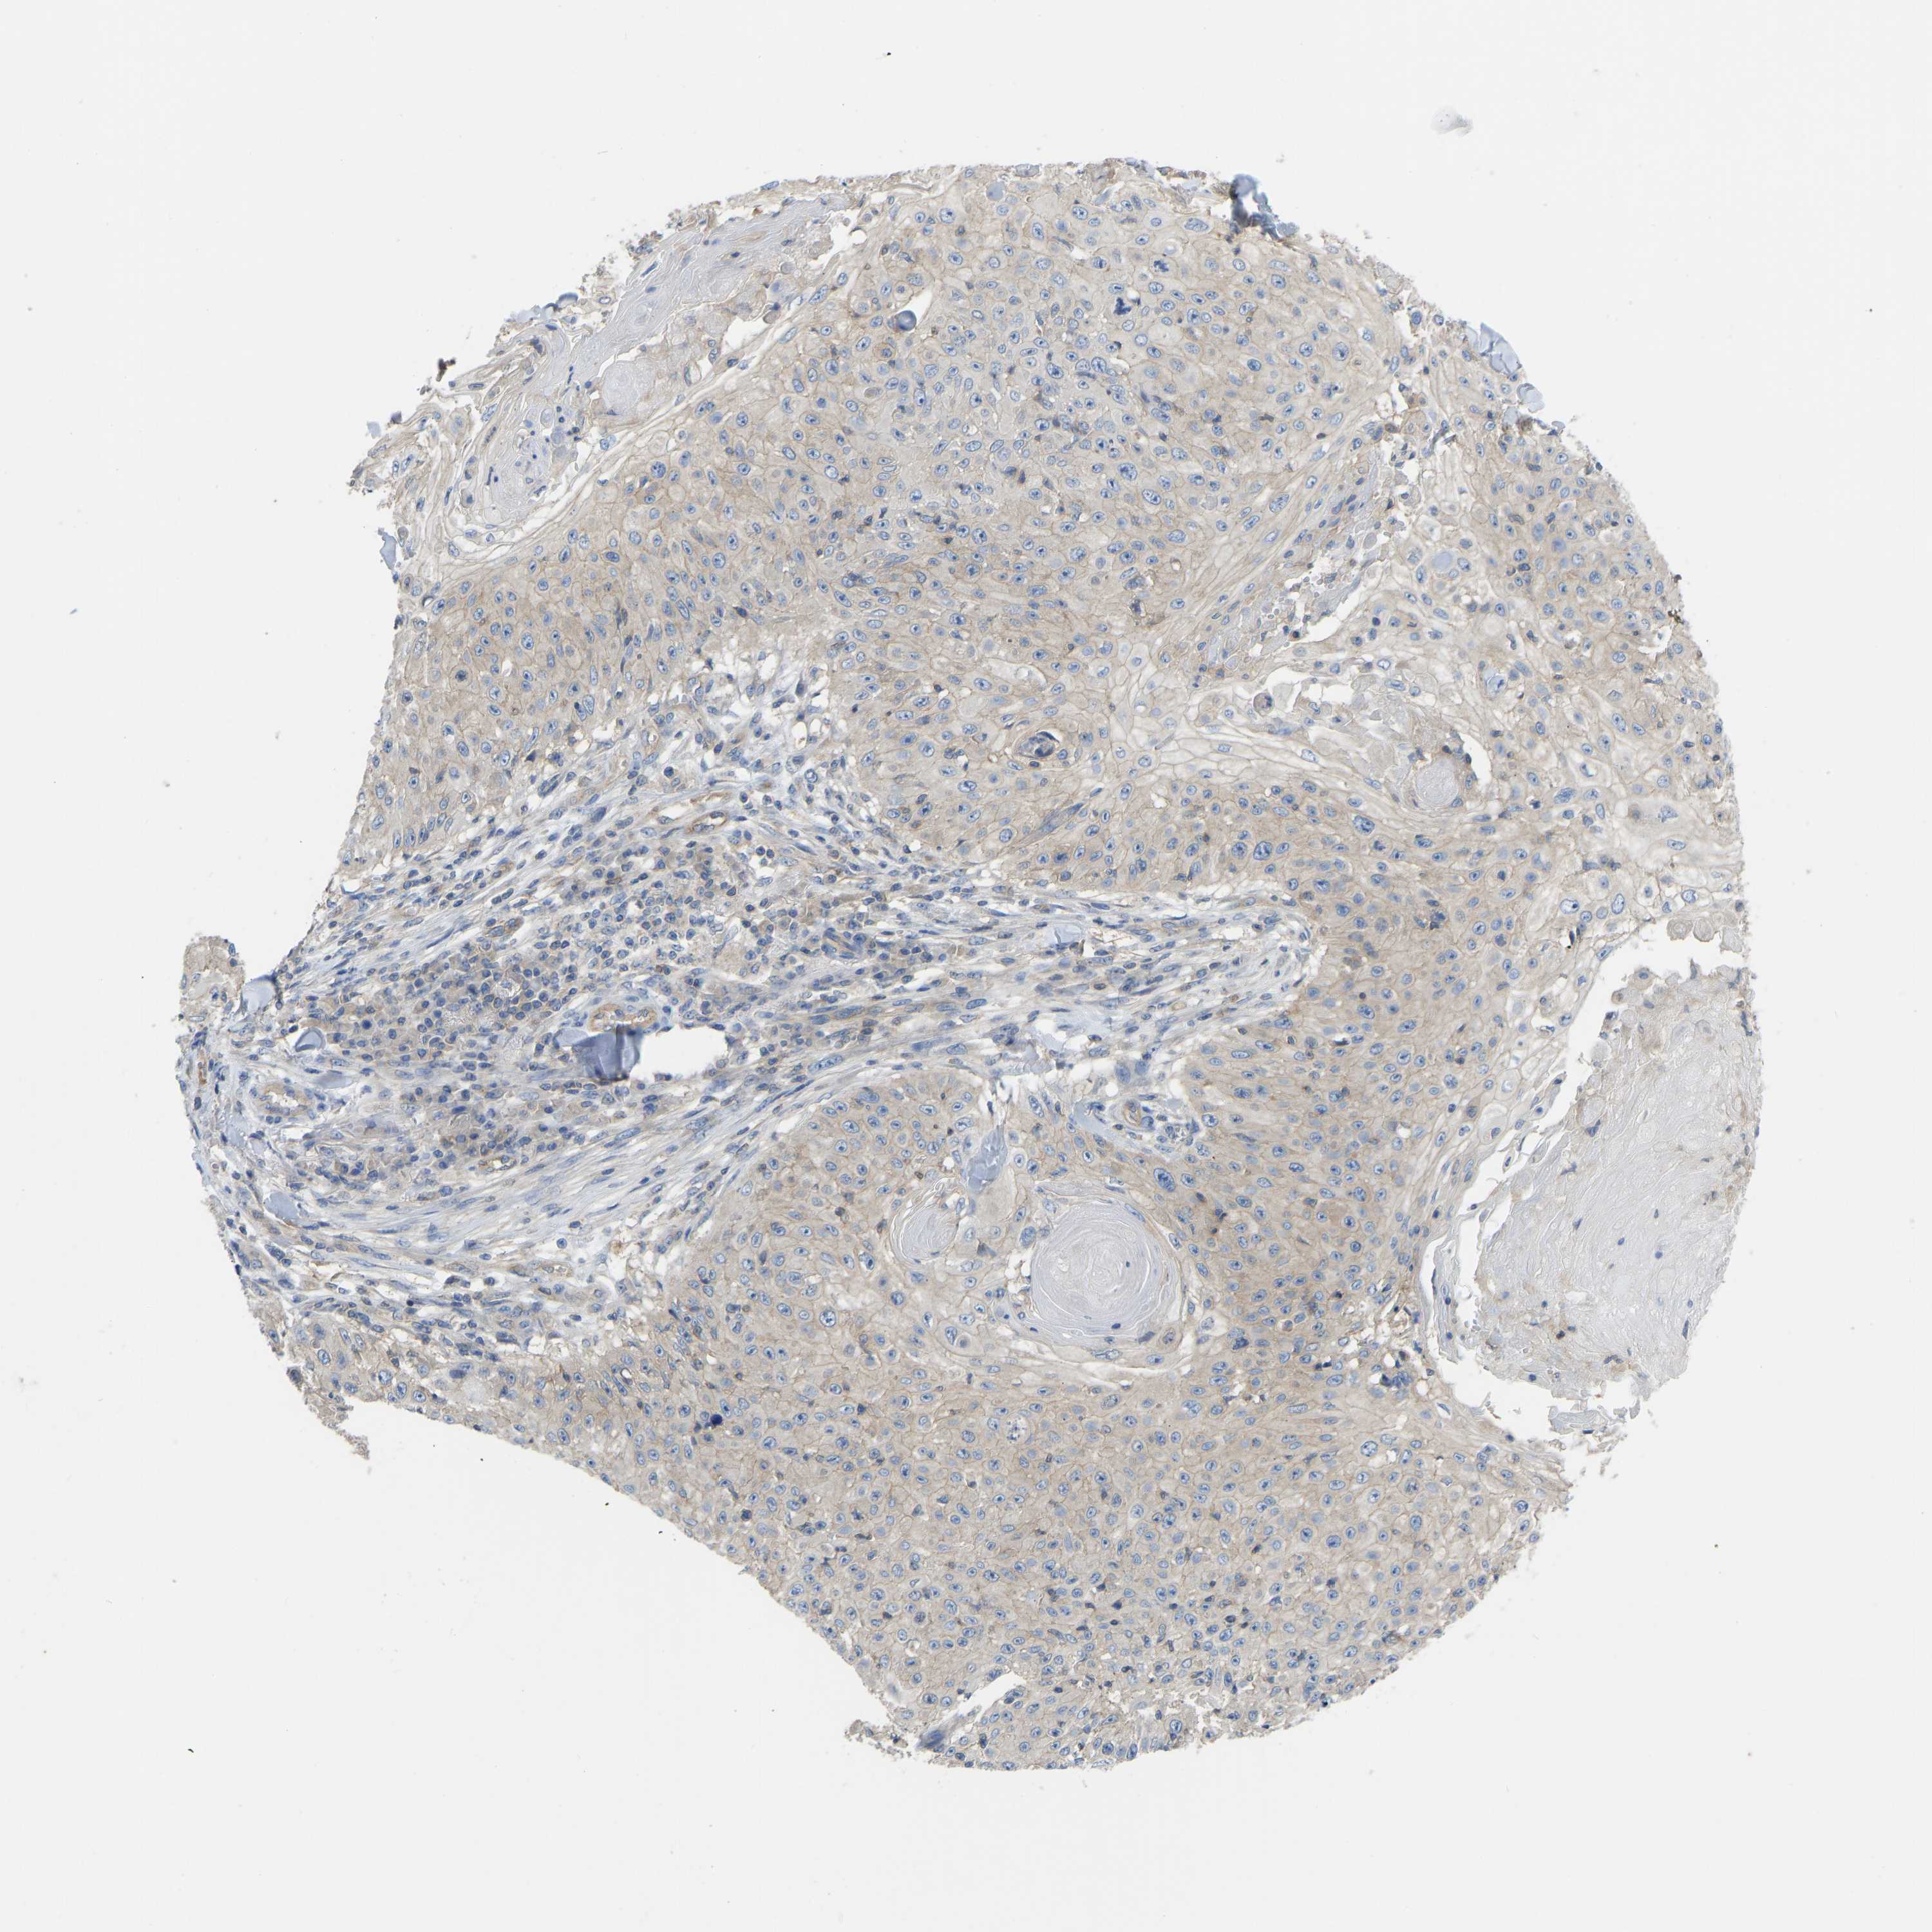

SKIN CANCER - Protein expressioni

A mouse-over function shows sample information and annotation data. Click on an image to view it in a full screen mode. Samples can be filtered based on level of antibody staining by selecting one or several of the following categories: high, medium, low and not detected. The assay and annotation is described here.

Antibody stainingi

Antibody staining in the annotated cell types in the current human tissue is reported as not detected, low, medium, or high, based on conventional immunohistochemistry profiling in selected tissues. This score is based on the combination of the staining intensity and fraction of stained cells.

Each image is clickable and will lead to virtual microscopy that enables deeper exploration of all samples and also displays staining intensity scores, fraction scores and subcellular localization as well as patient and tissue information for each sample.

Antibody CAB018581

Squamous cell carcinoma, metastatic, NOS